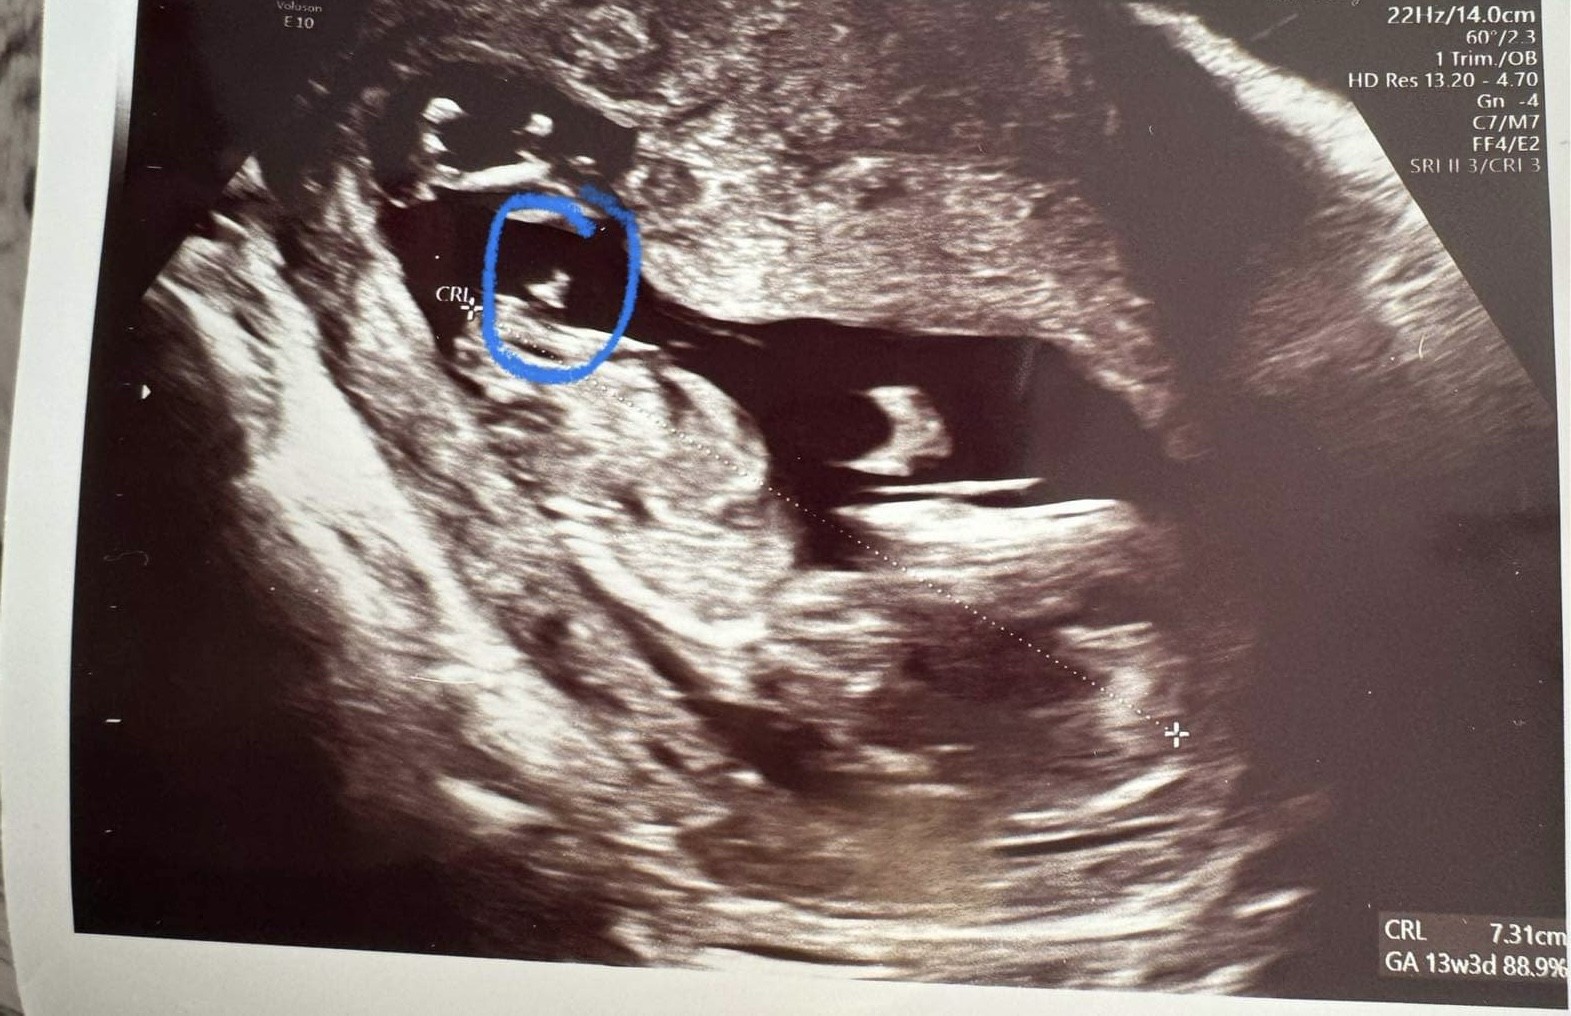

Dla mnie też bardziej dziewczynka 🤔 zobacz jak to u mnie wyglądało -

Na pierwszym chłopiec na drugim dziewczynka (równolegle do kręgosłupa)

• IMG_6770.jpeg

IMG_6770.jpeg

1,5 MB · Wyświetleń: 180